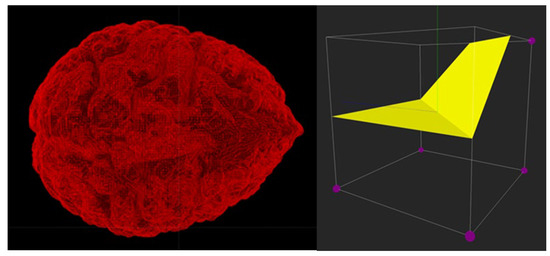

A scalar field is a function that assigns numbers such as densities and attenuation to points in R3. For volume visualization, computer graphics make use of implicit surfaces (isosurfaces) that are explicitly defined via field functions. There are many techniques for constructing isosurfaces from scalar fields, such as Delaunay triangulations [48] and marching cubes [49]. VanityX makes use of the marching cubes algorithm to construct isosurfaces via triangle meshes from volumetric data acquired from CT and MRI scanning devices.

With reference to Figure 16, we show a 3D surface-based model that is triangulated using the marching cube algorithm. The model represents a triangle mesh of a human brain triangulated from a free volumetric model. Triangle meshes in VanityX are implemented via DirectX triangle lists. A triangle mesh must be two-manifold, where each edge is shared by two faces—only boundary edges may belong to one face. Traversal to neighboring faces is allowed only through edges, and passing through vertices is not allowed.

In some cases, triangle meshes generated by the marching code algorithm are not two-manifold and therefore might be rendered with holes, so we developed a simple 3D tool to visualize marching cubes cases and spot potential errors. The right picture in Figure 16 shows a case where five voxels have bigger values than the threshold, and we use three triangles for creating a part of the isosurface.

Figure 16. On the left, we show a triangulated human brain. The model is rendered in the wire-frame mode without back culling. On the right, we inspect a marching cubes case. Two polygons (three triangles) are used to cover five voxels.